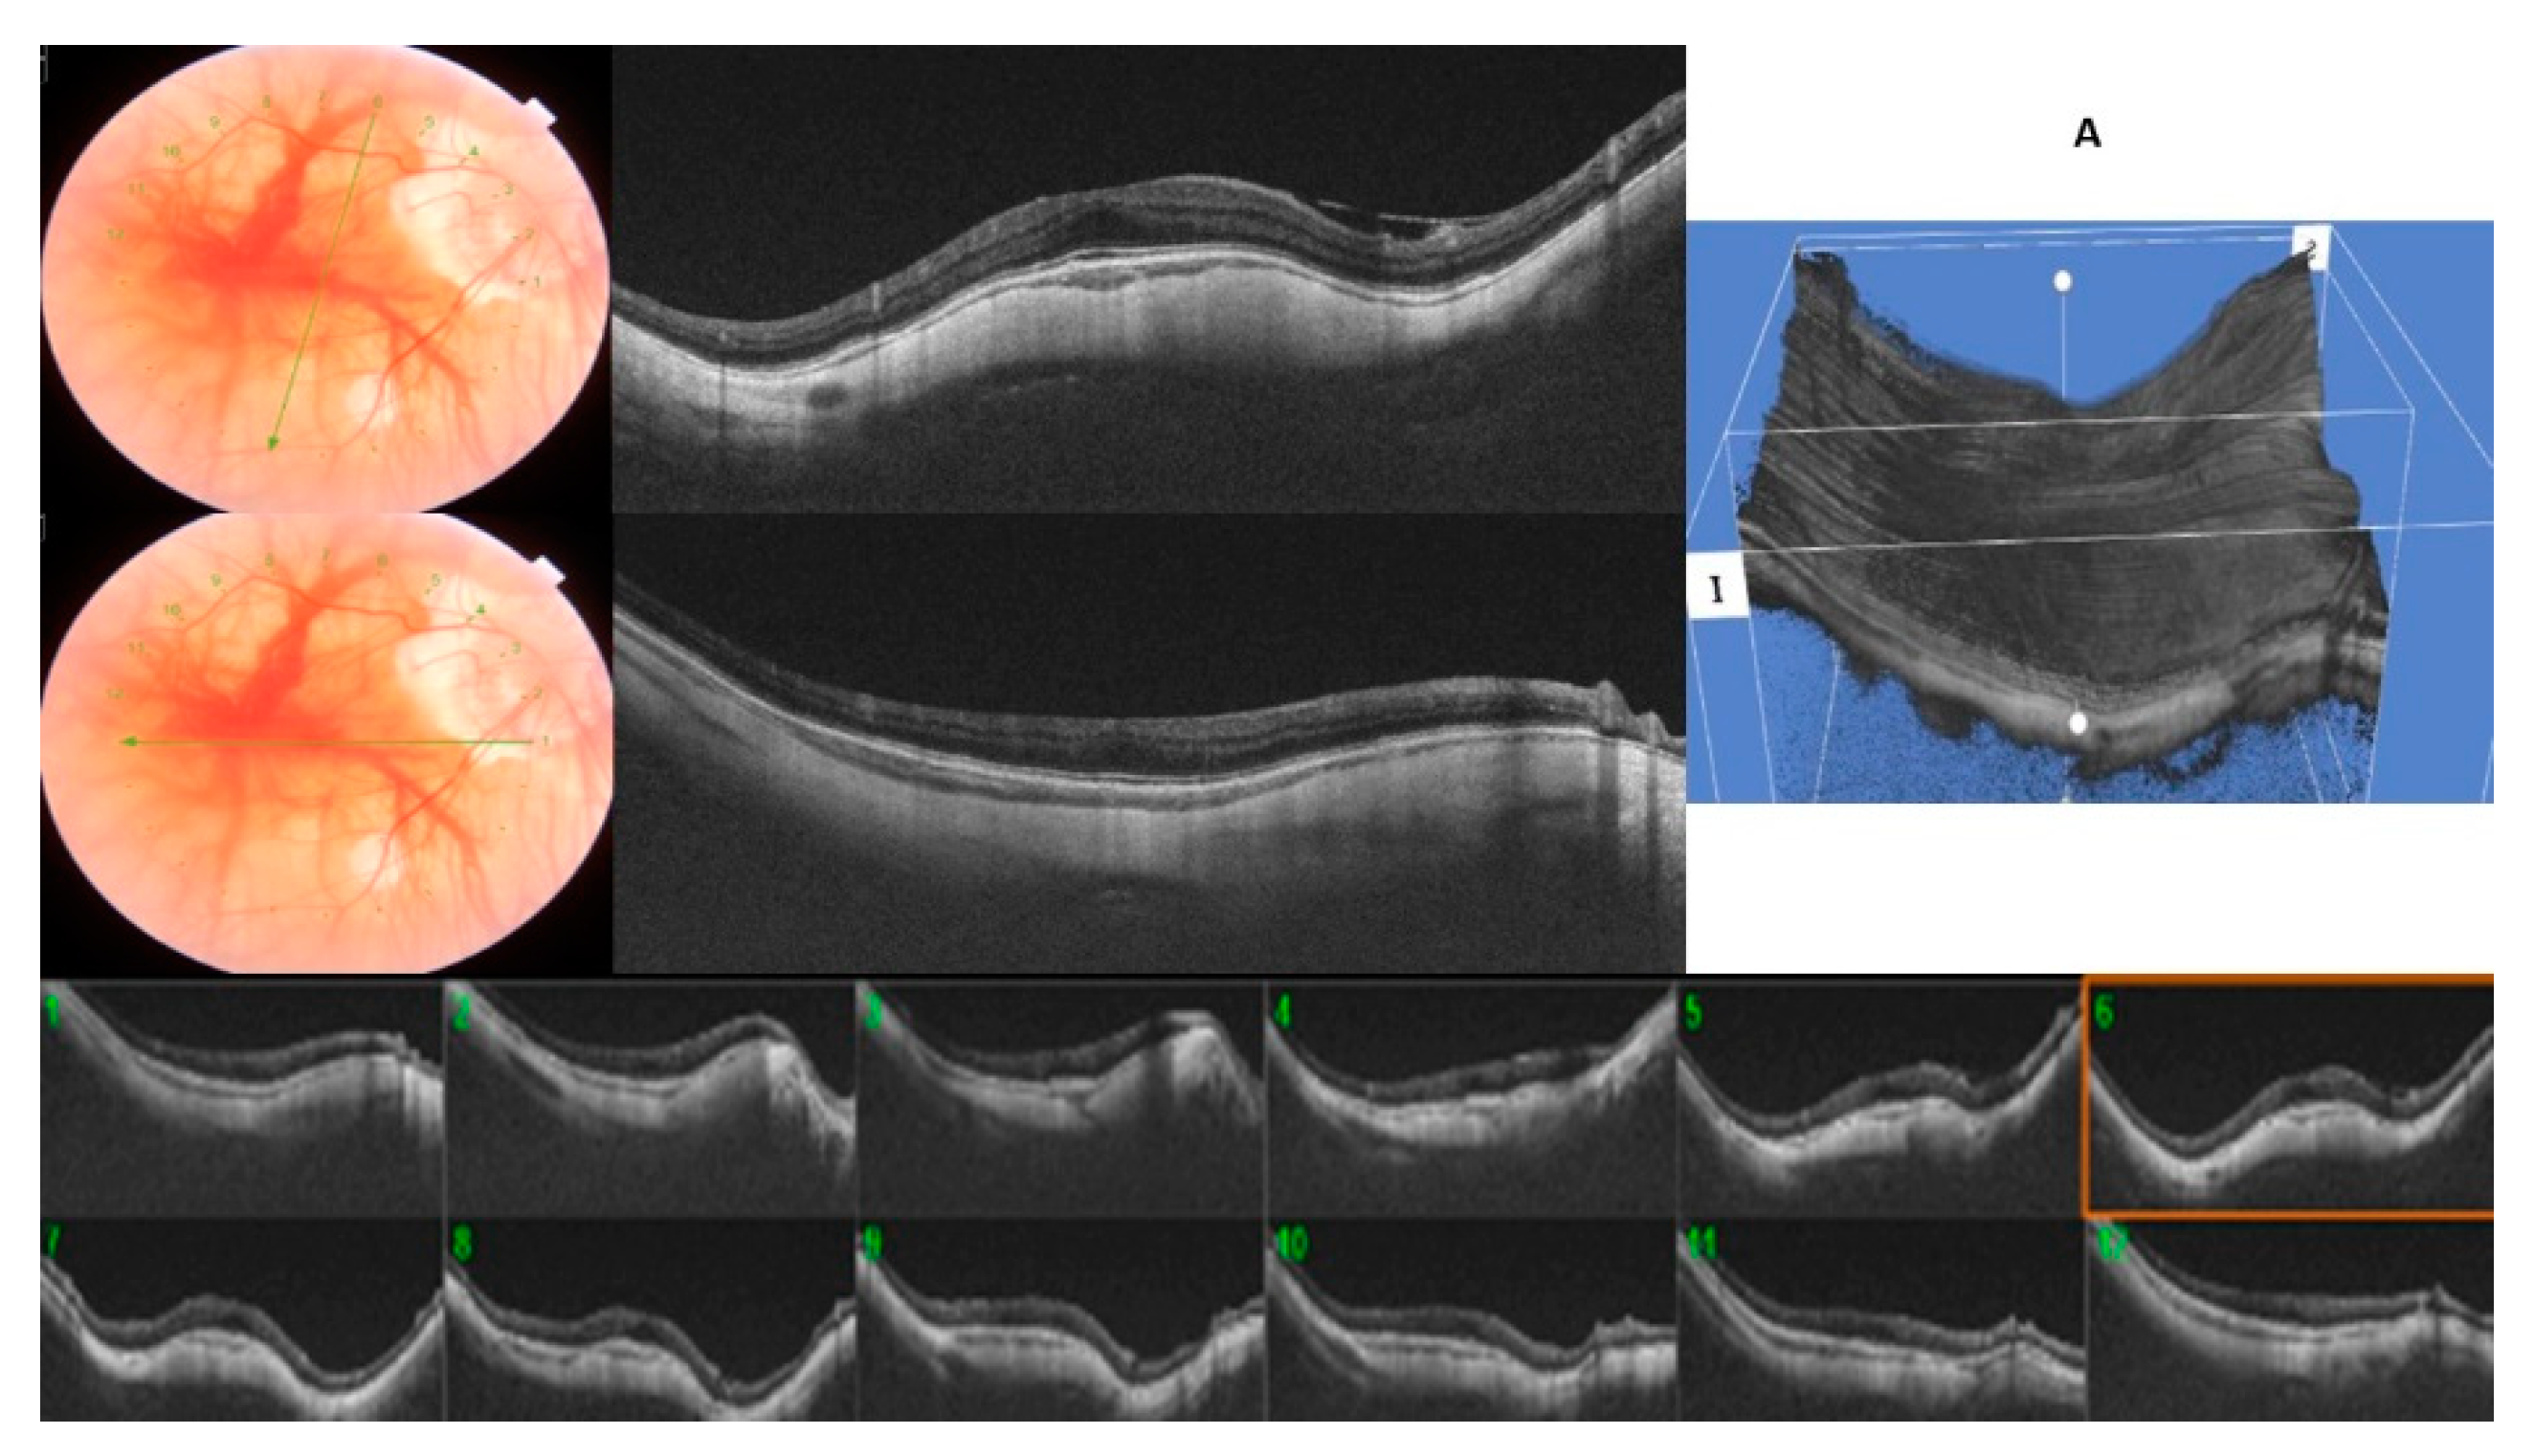

A typical round dome-shaped macula, with the 12 radial OCT scans centered on the fovea showing an elevation of ≥50 µm, was found in 12 eyes (24.4%), defining the DSM group (Figure 2). However, despite being round, all of them presented a predominant orientation, with some scans displaying a higher bulge than the opposing scans. Nine eyes of the DSM group showed a predominant horizontal orientation (75%) versus three eyes that showed a higher bulge in the vertical orientation (25%).

In the RSM group, we included those 37 eyes (75.6%) with <12 OCT radial scans affected. The mean of the OCT scans that showed an inward elevation ≥50 µm was 5.75 ± 1.69. Twenty-six eyes (70.2%) showed only an inward convexity in the horizontal direction manifested across the vertical OCT radial scans, whereas the opposite scans were flat, being classified as horizontally oriented RSM (Figure 3A). Ten (27.0%) eyes showed this inward convexity only in the vertical direction across the horizontal OCT radial scans, fulfilling the definition of a vertically oriented RSM (Figure 3B). One eye (2.7%) was classified as obliquely oriented RSM. The inward convexity occurred bilaterally in 17 eyes (34.6%). In four patients (8.1%), one eye showed the typical round dome-shaped convexity and the other eye showed a ridge-shaped band.

Figure 3. (A)/(B): A ridge-shaped macula (RSM) with six radial OCT scans centered on the fovea showing an inward convexity of ≥50 µm, whereas the macular curvature was unremarkable on opposite perpendicular meridians. (A): horizontally oriented RSM. (B): vertically oriented RSM.